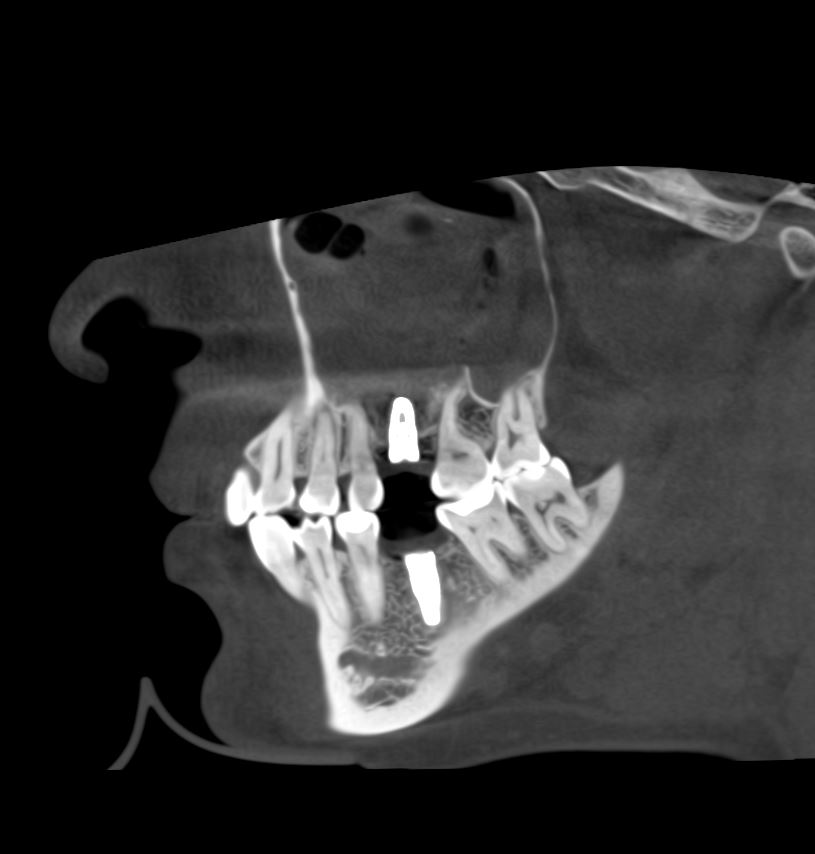

Если сделать КЛКТ на этом этапе (через 2-3 недели после операции), то иногда мы можем увидеть утолщение слизистой оболочки в области дна альвеолярной бухты, вплоть до рентгенологической картины гайморита:

однако, в течение последующего месяца (при соответствующей терапии) рентгенологическая картина возвращается к нормальной: